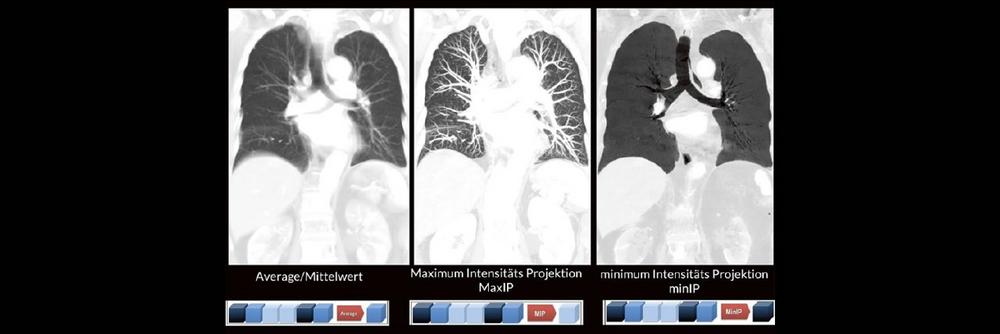

Darüber hinaus werden die unterschiedlichen MPR-Techniken wie z. B. Maximum Intensitäts- Projektionen (MaxIP´s) und minimum Intensitäts Projektionen (minIP´s) oft nicht routinemäßig angewendet. Dabei können verschiedene Pathologien durch den zielgerichteten Einsatz der unterschiedlichen MPR-Techniken oft viel einfacher und besser diagnostiziert werden.

• Maximum Intensität Projektion

• Minimum Intensität Projektion